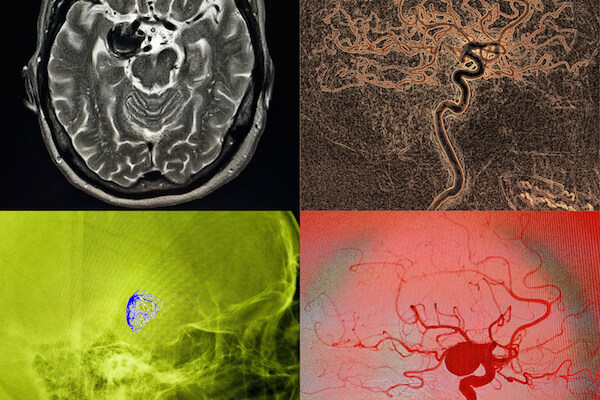

- embolizzazione di aneurismi cerebrali attraverso la tecnica del coiling o l’impianto di flow diverter

- embolizzazione di MAV (malformazioni arterovenose), FAV (fistole arterovenose) o FAVD (fistole arterovenose durali, ovvero fistole localizzate nello spessore durale)

- stenting intracranico (sia per il trattamento delle stenosi cerebrali che per l’assistenza all’embolizzazione di aneurismi)